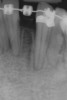

Figure 7  Radiograph of residual ridge defect in site No. 22.

Figure 7

The patient had no medical concerns and had a history of an implant placement in December 2002 when she was 25 years old. In February 2005, she presented with a mobile implant and an associated advanced peri-implantitis. Radiographic review at the initial examination demonstrated significant destruction of the dentoalveolar ridge around the implant as well as around the adjacent natural dentition. Emergency-based treatment involved surgical implant removal only and debridement of the infection (Figure 4 and Figure 5). Following uneventful healing, an advanced ridge defect was apparent at the edentulous site and moderate and advanced attachment loss noted at No. 22D and No. 21M, respectively (Figure 6 and Figure 7). This case demonstrates bone loss of two separate origins: lack of bone because of tooth agenesis and destruction of bone from inflammatory peri-implantitis.

Figure 3  Preoperative radiograph of the failing implant in the site of tooth No. 22.

Figure 3